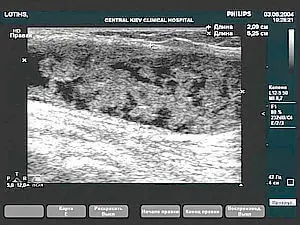

Суглобовий хрящ колінного суглоба. Артроз: висота хряща знижена